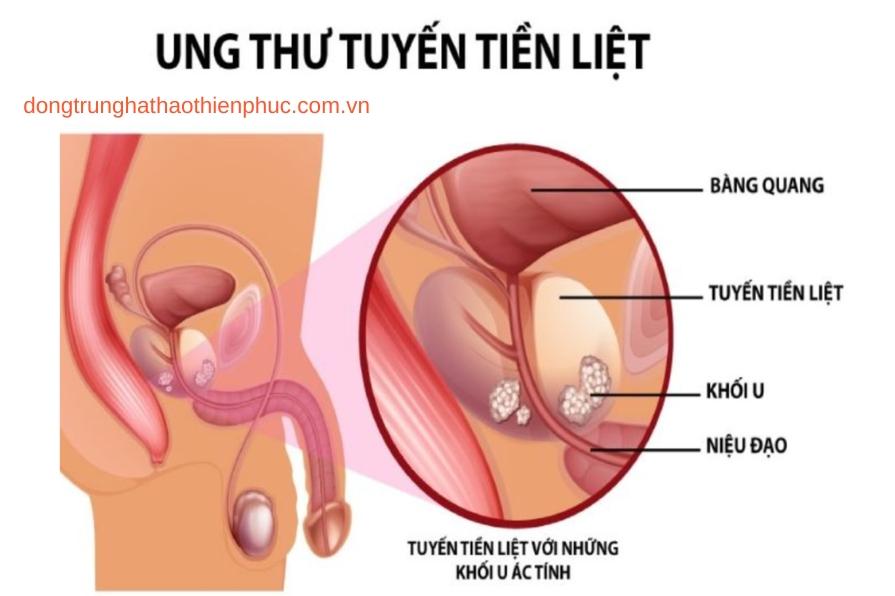

Ung thư tuyến tiền liệt là một trong những bệnh lý phổ biến nhất ở nam giới, đặc biệt là những người trên 50 tuổi. Bệnh có thể được điều trị hiệu quả nếu được phát hiện sớm. Bài viết này sẽ cung cấp thông tin chi tiết về ung thư tuyến tiền liệt, bao gồm nguyên nhân, triệu chứng, phương pháp điều trị, và cách phòng ngừa hiệu quả.